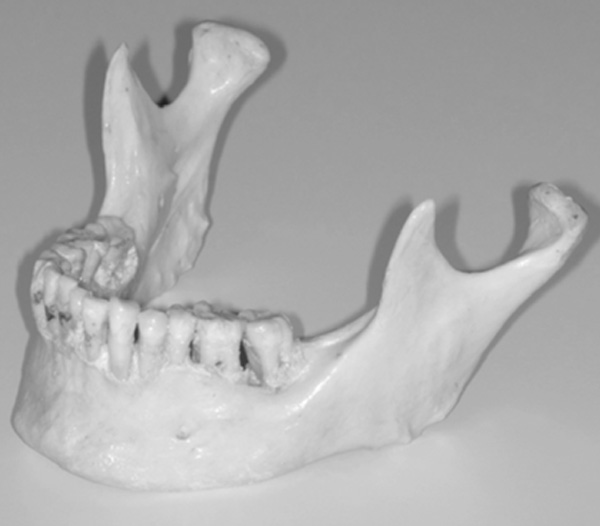

To critically evaluate in further studies the usefulness for measuring asymmetric mandibular shapes as well as linear and angular measurements from digital panoramic radiographs, a technique for producing STL mandibles with known amounts of asymmetry was devised from by scanning an original skull mandible (Fig. 1) and artificial asymmetries were produced using a CAD software. The following section describes the methodology used.

Original skull mandible.

The preliminary information required to generate the synthetic mandibles was obtained by scanning the original skull mandible as seen in (Fig. 1) using a Zephyr® 3-D non-touch laser scanner (Kreon model KZ 50, Limoges, France). The Zephyr® KZ 50 was mounted on a Faro® arm, Titanium series (Kreon, Limoges, France). The Zephyr® laser scanner registers up to 28,800 points per second with a resolution of up to 10 um and a measurement frequency of 60 images per second with 480 points per image. The Faro® arm, Titanium series, is a six axis mounting arm with an accuracy of 12 um. The arm assembly allowed for a convenient and efficient method of capturing the surface images of the skull mandible with a high resolution and accuracy given the combined specifications.